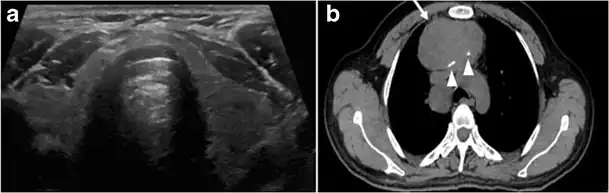

Thyroid scanning with technetium-99 m (Tc99m) plays an important role in detecting orthotopic and ectopic thyroid tissue. Both CT scans and US can help detect ectopic tissue when a lesion demonstrates imaging and enhancement characteristics of thyroid tissue. The absence of normally sited thyroid gland in US and CT scans also supports the diagnosis. In addition, US can guide FNA for cytological confirmation of a thyroid lesion. Ectopic thyroid tissue appears as a well-circumscribed, homogeneous, highly attenuating mass relative to adjacent muscles. Normally, it enhances avidly following the administration of iodinated contrast.[1]

Ectopic thyroid tissue may be detected in the tongue near the foramen cecum (90%) and along the midline between the thyroid isthmus and posterior tongue, lateral neck, mediastinum, and oral cavity. The most frequent location is the base of the tongue (Figs. 16, 1717 and and18).18). In 70% of cases, the ectopic thyroid is the only functional thyroid tissue present in the body (Fig. 18).[1]

Fig. 17. Ectopic thyroid on the left parotid gland with a palpable left parotid mass in a 69-year-old male patient. a, b Axial and coronal enhanced neck CT scan demonstrates well-defined homogeneous enhancing mass (white arrows) within the left parotid gland with preserved surrounding fat planes. It also shows a normal thyroid in normal position in the lower neck. c Image taken 20 minutes after 5 mCi injected Tc99m-Pertechnetate shows normal thyroid uptake of tracer and physiological uptake in the salivary glands (short black arrow). There is a distinct focus of abnormal tracer accumulation in the left parotid/submandibular region. Patient was given lemon juice with evident normal washout from the salivary glands and relative retention by this abnormal focus (long black arrow).[1] -

Fig. 18. Lingular thyroid in a 33-year-old male who presented with oropharyngeal bleeding. an Axial enhanced neck CT scan at the level of mandible demonstrates a 3 × 3 × 3.4 cm round, partly well-delineated, heterogeneously enhancing lesion (white arrow). It is predominantly on the left side of the oropharynx and to some extent at the mid part of the base of the tongue. The thyroid gland was normal (not shown). b Image of the anterior face and neck taken 20 minutes after Tc99m-Pertechnetate injection shows absent thyroid radiotracer uptake in normal thyroid anatomical location (black short arrows). There is an area of increased uptake (long black arrows) corresponding to the posterior tongue mass identified on CT scan.[1]

Ectopic thyroid tissue lateral to the orthotopic midline location is rare. The exact anatomical definition of this rare entity is debated in the literature. To avoid confusion, some authors define a lateral neck ectopic thyroid as any thyroid tissue superficial to the strap muscles with no midline continuity. The majority of lateral thyroid ectopia cases have been reported as lesions closely related to the strap muscles. There are few reported cases of ectopic lateral thyroid tissue in the submandibular region, jugulodigastric region, or within the parotid gland substance (Fig. 17).[1]